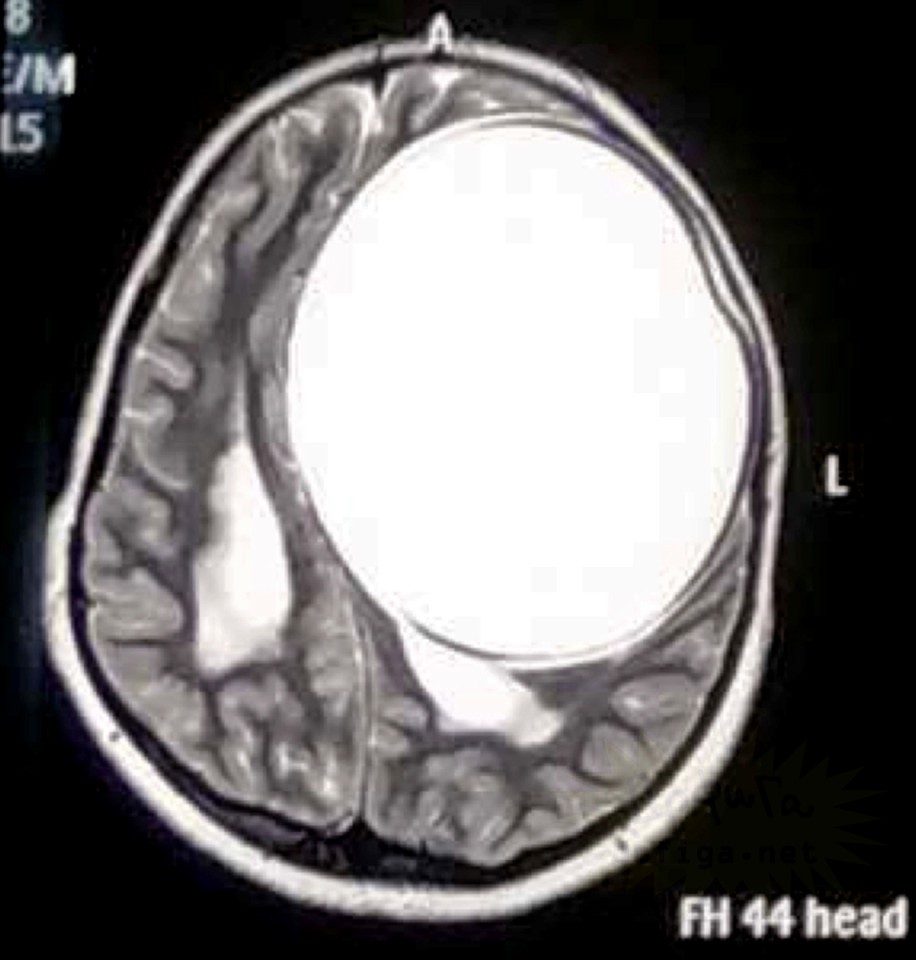

gif_animation インドにて、12歳の女の子の身体(脳部分)から、寄生虫の卵、675gが取り出された。頭痛に苦しんでいたという女の子。感染源は不明である。[7]images